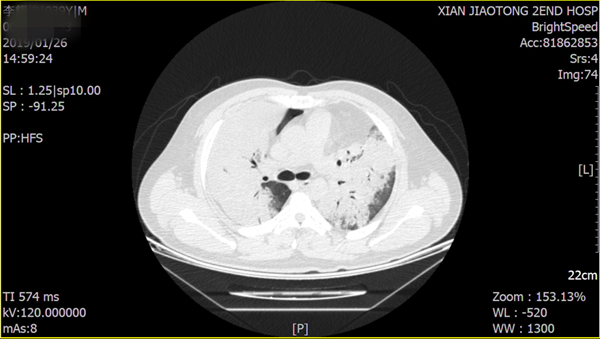

患者的胸部CT影像

近日,我院呼吸与危重症医学科杨拴盈主任、张德信副教授成功给1例弥漫性肺疾病患者行TBCB检查,取材过程顺利,取材量充足。文献检索提示,该患者是西北地区首例应用TBCB技术成功获得组织学标本的病例。该项技术在我院的成功开展使得我院呼吸与危重症医学科对弥漫性肺疾病的诊断更精准、更微创、费用更低,同时进一步促进我院呼吸介入病学的发展,为更多弥漫性肺疾病患者的诊治创造条件。